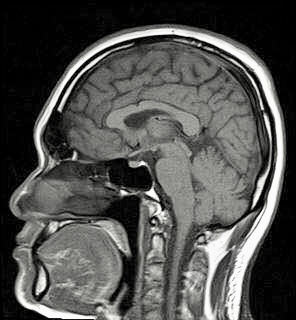

เมื่อร่างกายมีความผิดปกติจากภายใน บางครั้งการตรวจวินิจฉัยแบบธรรมดาก็ไม่สามารถแสดงผลที่ต้องการได้ปัจจุบันวงการแพทย์ได้นำเครื่องตรวจด้วยสนามแม่เหล็กแรงสูง หรือ เอ็ม.อาร์.ไอ (MRI) ซึ่งเป็นเครื่องมือบันทึกภาพทางการแพทย์ โดยการส่งถ่ายพลังงานคลื่นวิทยุจากขดลวดส่งคลื่นความถี่วิทยุไปยังผู้ป่วย ซึ่งนอนอยู่ในสนามแม่เหล็กแรงสูง พลังงานเหล่านั้นจะสะท้อนกลับมายังตัวรับสัญญาณ โดยสัญญาณที่สะท้อนกลับมาจะถูกเปลี่ยนแปลงตามคุณสมบัติของเนื้อเยื่อและหลอดเลือด ซึ่งการเปลี่ยนแปลงเหล่านี้ก็คือข้อมูลสำหรับการสร้างภาพโดยคอมพิวเตอร์ตามสรีระของผู้ป่วยจากส่วนร่างกายที่ถูกกระตุ้นด้วยพลังงานนี้ การตรวจด้วยวิธีนี้จะต้องใช้เวลาในการตรวจประมาณ 20-40 ซึ่งขึ้นอยู่กับอวัยวะที่จะตรวจ

การตรวจเอ็มอาร์ไอสามารถตรวจค้นหาโรคต่างๆในร่างการ เช่น โรคมะเร็ง เนื้องอก การอักเสบ ถุงน้ำ นิ่วในไต หรือกระเพาะปัสสาวะ ทางเดินน้ำดีอุดตัน หนองในโพรงจมูก หลอดเลือดตีบ หลอดเลือดโป่งพอง หลอดเลือดแตก หลอดเลือดตีบ หลอดเลือดโป่งพอง ลิ้นหัวใจรั่ว กระดูกแตก ข้ออักเสบ เอ็นอักเสบ หมอนรองกระดูกทับเส้นประสาท กระดูกสันหลัง(คอ/หลัง/เอว)เสื่อม มะเร็งต่อมลูกหมาก ต่อมลูกหมากโต เป็นต้น

สามารถตรวจวินิจฉัยอวัยวะได้

สมอง และเส้นประสาท ตา และเส้นประสาทตา รูหู โพรงจมูก คอ ไทรอยด์ ปอด ตับ ไต ม้าม ตับอ่อน ถุงน้ำดี มดลูก รังไข่ ต่อมลูกหมาก ข้อต่อต่าง(ไหล่/ข้อมือ/ข้อเท้า/เข่า/ข้อนิ้ว) กระดูก(แขน/ขา/เท้า) ระบบหลอดเลือดที่แขน/ช่องท้อง/ไต/ขา/ปลายแขนปลายขา/หลอดเลือดที่หัวใจ กระดูสันหลัง(คอ หลังและเอว)